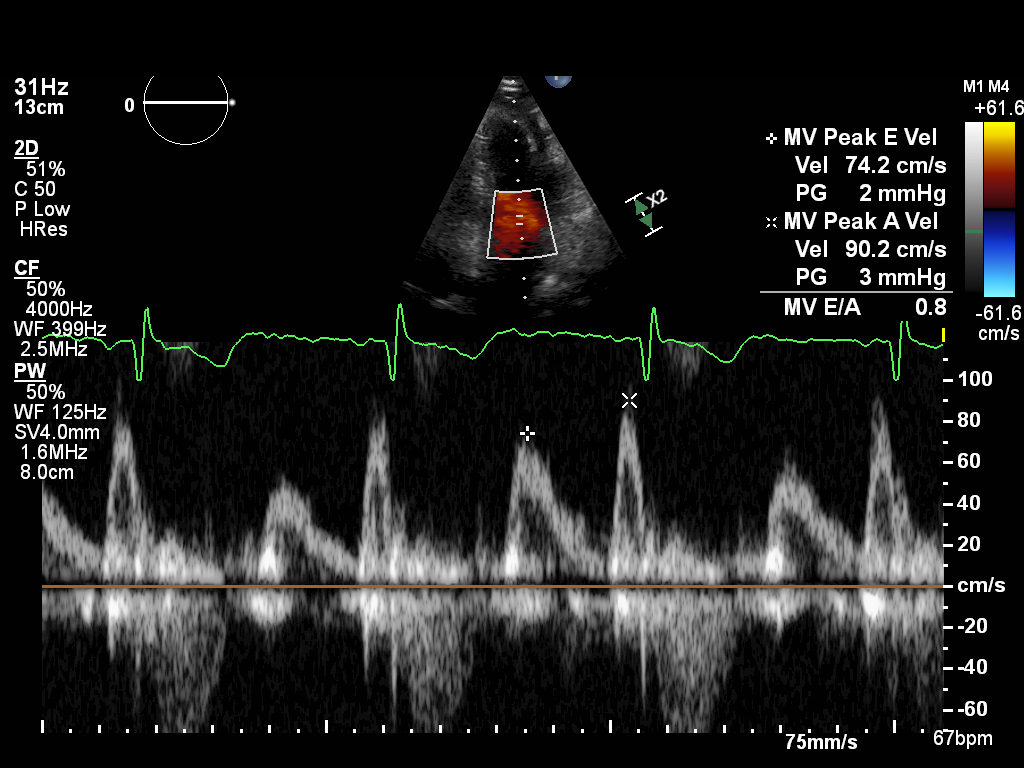

ImageView NameDescription

doppler-mv doppler-mv Spectral Doppler of the mitral valve